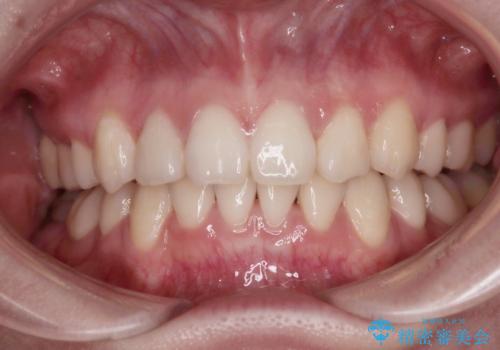

50代女性 八重歯を矯正治療 歯並びの中等度のがたつき

マウスピース矯正が煩わしい ワイヤー装置での非抜歯矯正

担当医 藤巻太一朗